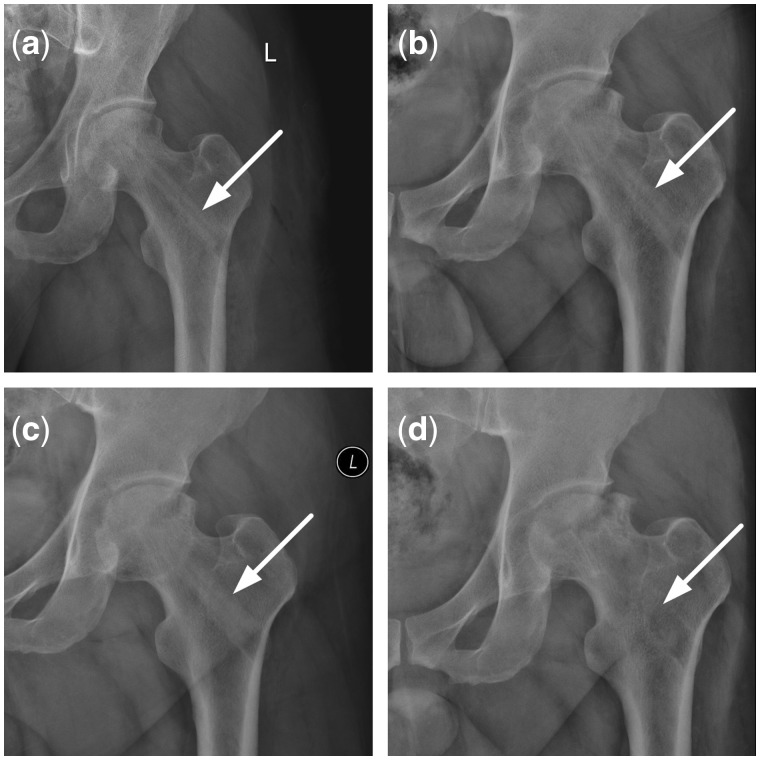

Both CR (Fig. 7) and CT (Fig. 8) showed that reconstruction rod contacted tightly with femoral head, femoral neck and intertrochanteric; however, the interface between the rod and host bone was very clear due to density difference between them after surgery. Twelve months later, the rod density reduced to similar to that of host bones, the interface between them became blurred. In addition, the inside diameter of rod looked bigger than that of after surgery.

Figure 7.

CR changes after implantation of the reconstructional rod. (a) CR in 3 days on postoperative; (b) CR in 3 months on postoperative; (c) CR in 5 months on postoperative; (d) CR in 12 months on postoperative